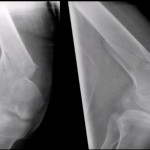

Panel Discussion on Hip fractures

Courtesy: Drs. Christopher Haydel, Matthew Lorei, Drew Brady, and Kenneth Graf

hip fracture panel discussion